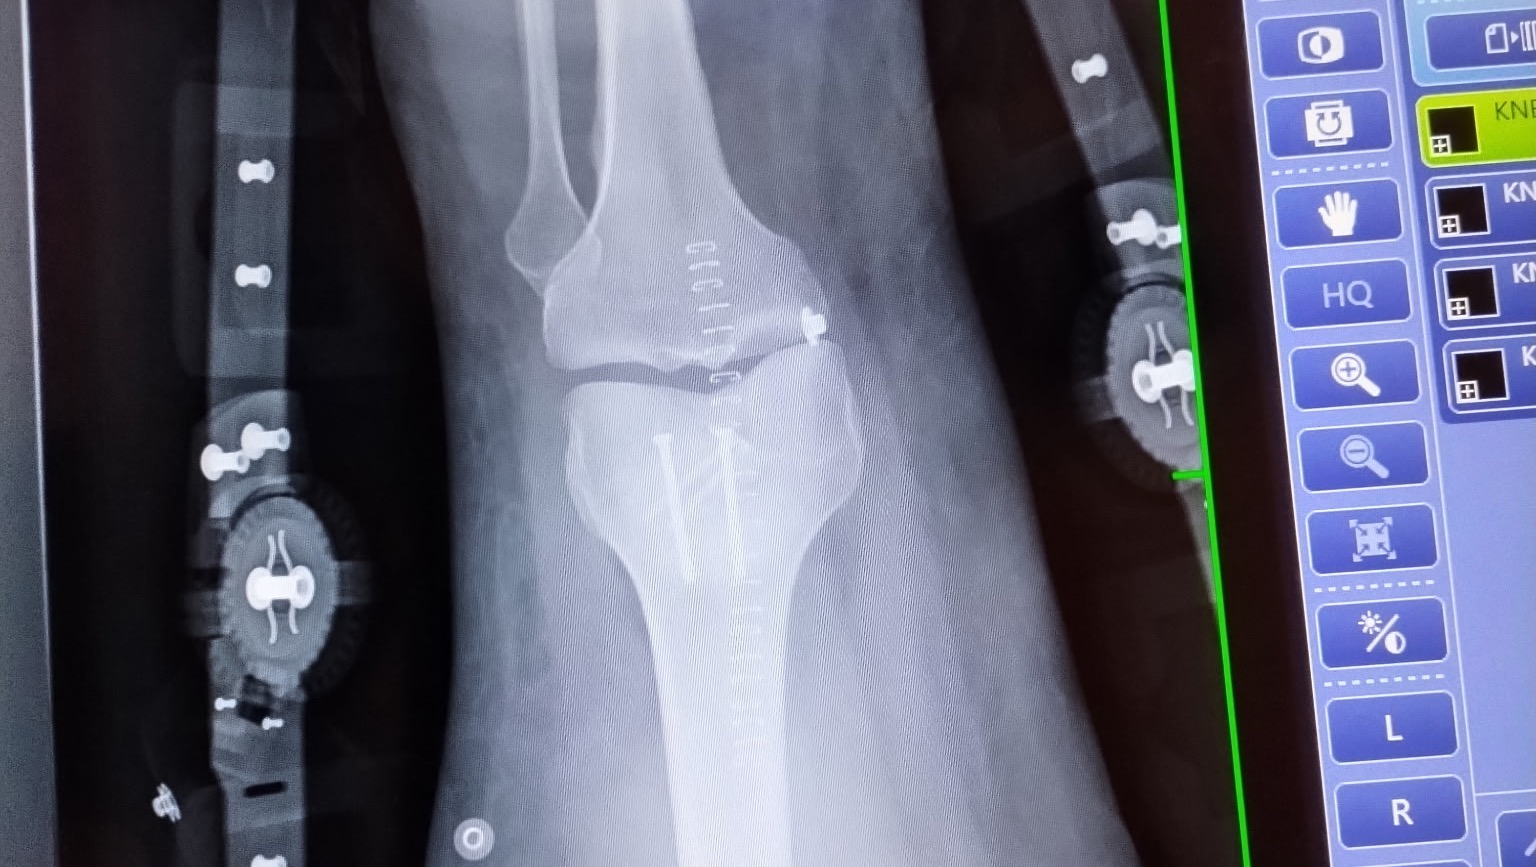

I have already had knee repair surgery, in which I got 4 screws to hold it together and 23 staples to seal the surgical site. I am on the long road to recovery. Due to this injury, I am not currently allowed to work. With winter coming I am in need of assistance with covering my monthly costs while I recover. Over the next several months, I will need to learn to walk again.